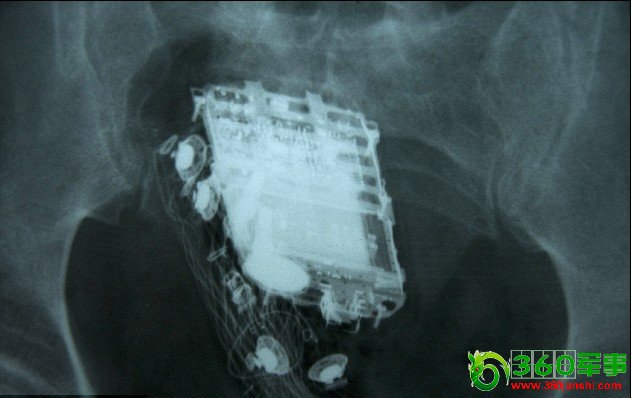

X射线扫描显示,手机被深深地塞进了直肠里。